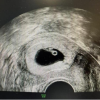

Part 3: 静待花开,终迎生命奇迹